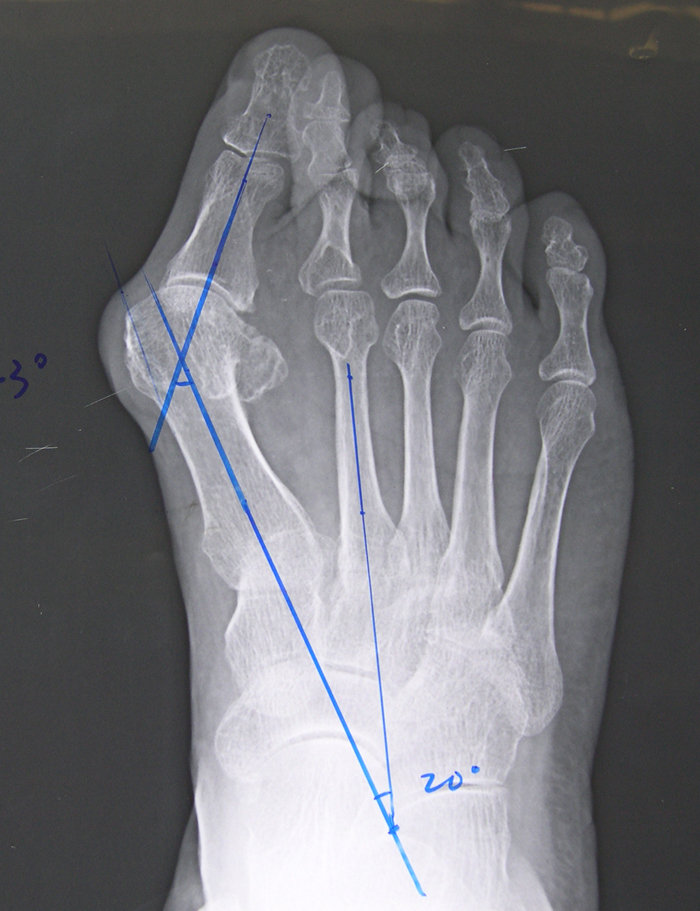

随后仔细了检查患者的足趾畸形,为患者拍了片子,确诊为双足拇外翻畸形,好在不算严重,通过简单的支具就可以治疗。

又称“脚孤拐”,医学专业术语称拇外翻畸形,是足部一种常见的畸形,女性多发,男女发病率为1:20,到底外翻到什么程度才算拇外翻呢?通常认为一般认为超过15度。

关于拇外翻的手术治疗术士多达上百种,应该根据患者的年龄、工作性质、畸形的严重程度等多种因素采取不同的治疗方式,术前需要进行拍片等多项检查进行综合评估,请选择您信任的医生进行手术治疗!